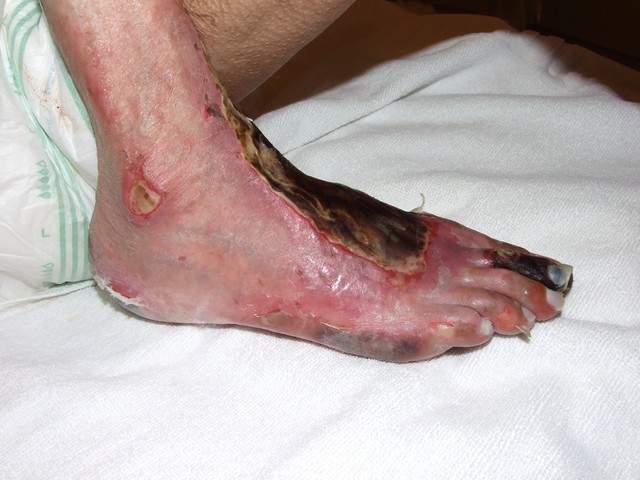

Necrosis y momificación del pie